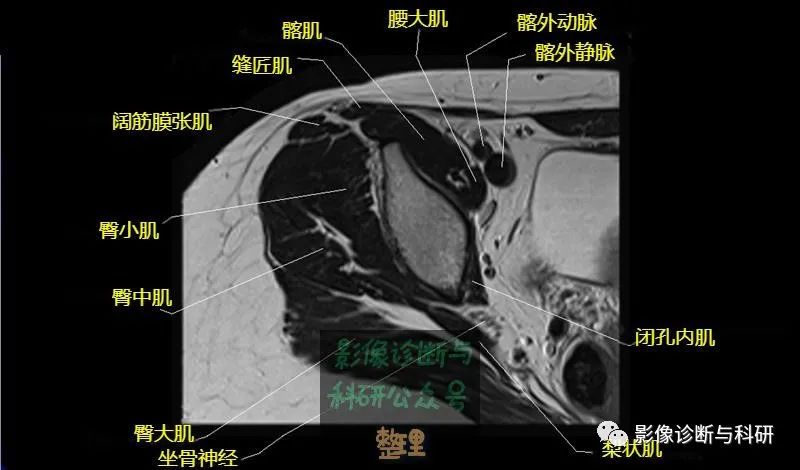

髋关节MR轴位详细标注